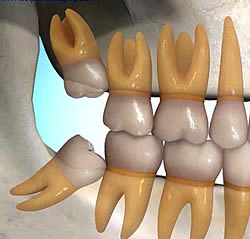

Ortodontik nedenler:

Tamamlanmış bir diş arkında yer olmaması durumunda sürmekte olan yirmi yaş dişleri ark formunu bozup çapraşıklığa sebep olacaksa çekilmeleri gerekir.